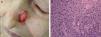

Existencia de lesiones cutáneas previas en la zona tumoral como úlceras crónicas, cicatrices por quemadura (fig. 1), queratosis actínicas o CCNM.

Diferenciación celular (figs. 2 y 3): bien diferenciado, moderadamente diferenciado, pobremente diferenciado.

En función de las características tumorales, se ha definido como carcinoma epidermoide de peor pronóstico o T2 aquel que ha cumplido con los criterios establecidos por la AJCC en la séptima edición de su manual13, es decir, tamaño>2cm (fig. 4) y/o al menos 2 de las siguientes características: localización en zonas de alto riesgo (pabellones auriculares o labios [fig. 5]), profundidad>2mm o Clark≥4, y diferenciación (tumores pobremente diferenciados).